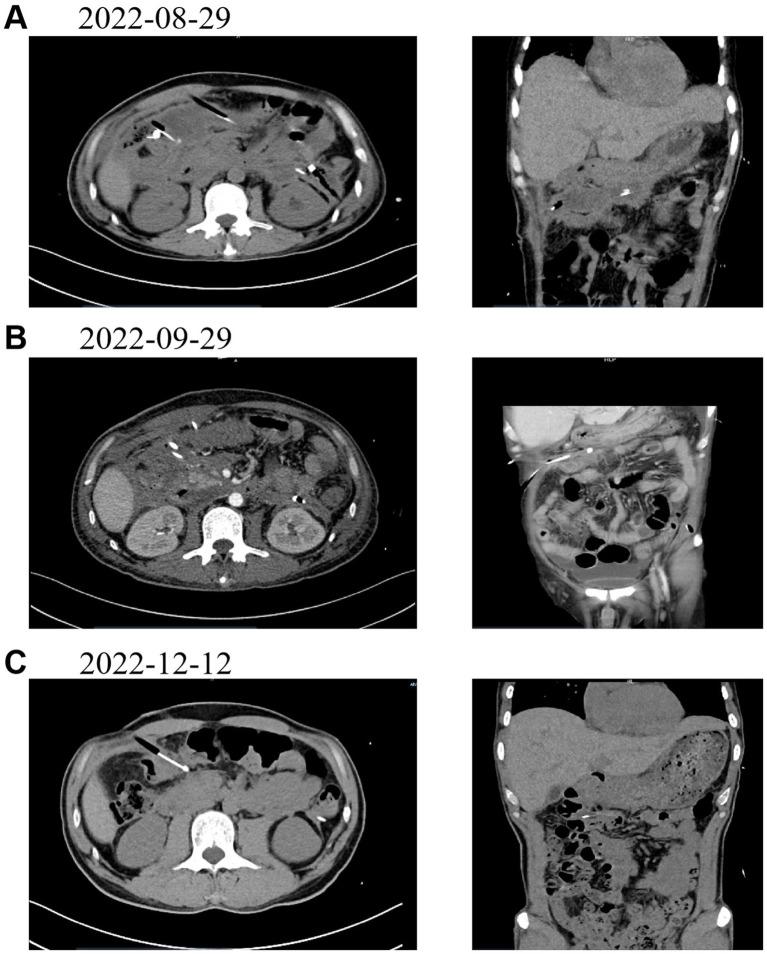

Multimodal imaging virtual fusion navigation offers higher accuracy and real-time guidance compared to single imaging modalities. This case report explores the value of contrast-enhanced ultrasound (CEUS)/CT fusion navigation in the localization, characterization, and interventional guidance of a hidden peripancreatic abscess in acute pancreatitis.

METHODS

The case involved the use of contrast-enhanced ultrasound and CT virtual fusion navigation to identify and assess the hidden peripancreatic abscess in a patient diagnosed with acute pancreatitis. The fusion technology allowed for real-time navigation during interventional procedures, offering improved lesion localization and characterization.

RESULTS

CEUS/CT fusion navigation successfully localized and characterized the hidden peripancreatic abscess. The real-time navigation provided by the fusion technology improved the accuracy and safety of the interventional procedure.